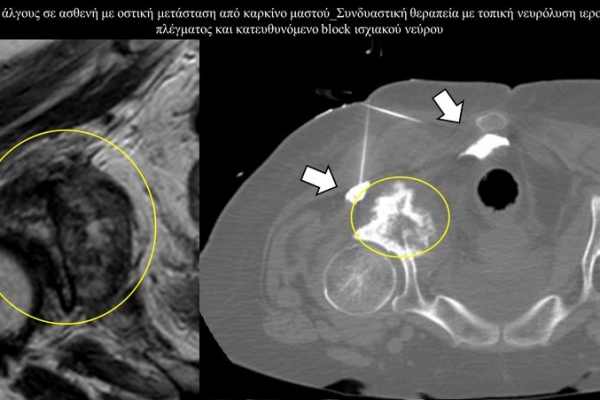

Η αντιμετώπιση του καρκινικού πόνου, εκτός από την κλασική συντηρητική φαρμακευτική θεραπεία, όταν ο πόνος επιμένει ή όταν οι παρενέργειες των φαρμακευτικών μεθόδων εξαντλούν τον ασθενή, περιλαμβάνει ελάχιστα παρεμβατικές τεχνικές με τις οποίες επιτυγχάνεται διακοπή ή καταστροφή της νευρικής οδού μεταβίβασης του πόνου. Η επεμβατική ακτινολογία διαθέτει μια πληθώρα θεραπευτικών τεχνικών που σκοπό έχουν να προσφέρουν ποιοτική βελτίωση της ζωής και των σχέσεων, τόσο των ογκολογικών ασθενών, όσο και των οικογενειών τους.